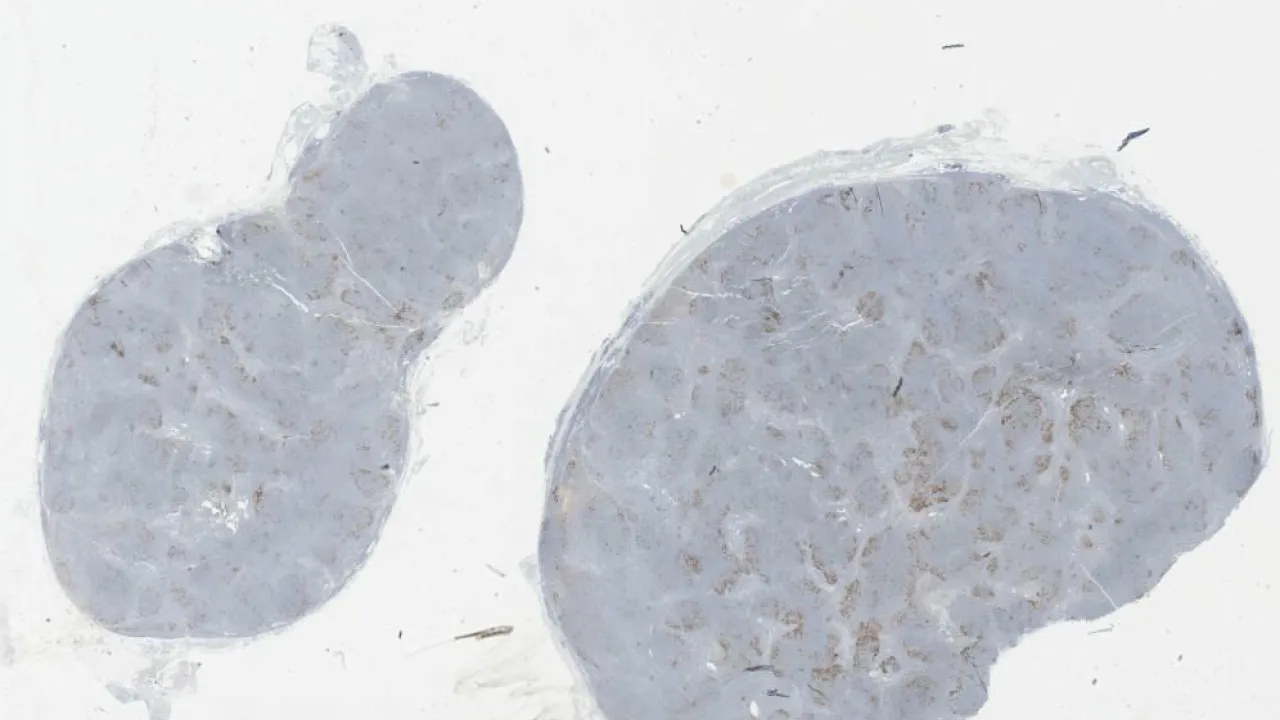

Lymph Nodes, Mantle cell lymphoma, CD23 stain